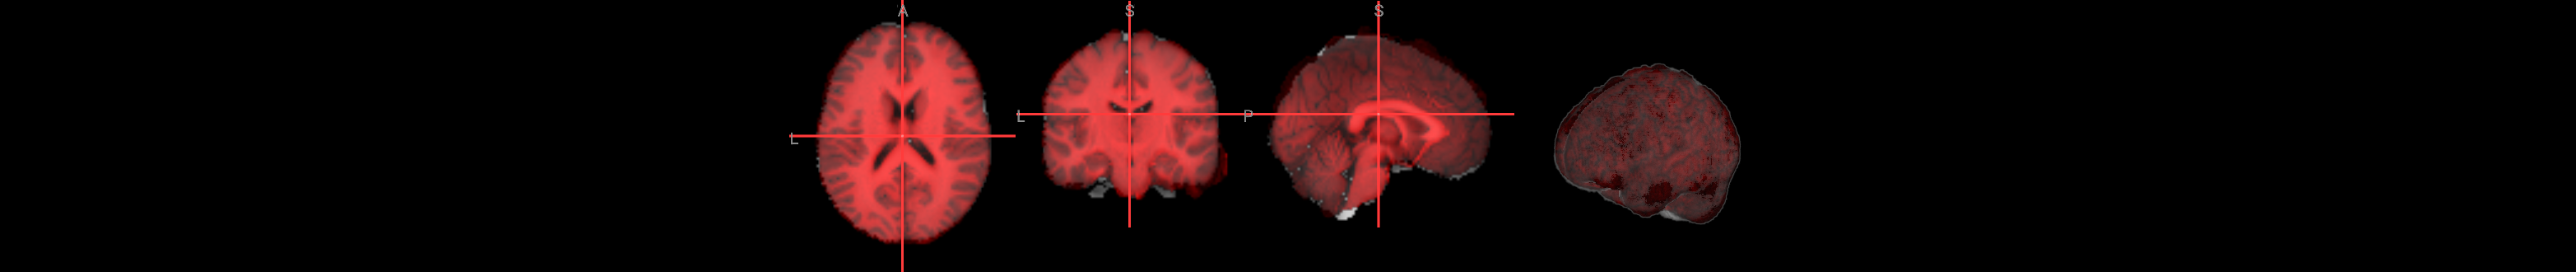

We will use ipyniivue to look at the data:

Many of the quality checks for the functional images are similar to those for the anatomical images. Look out for excessively bright or dark spots in the grey or white matter, as well as any image distortions, such as abnormal stretching or warping. A common area where slight distortion may occur is in the orbitofrontal region, just above the eyeballs.

Additionally, it’s important to check for excessive motion during the scan.